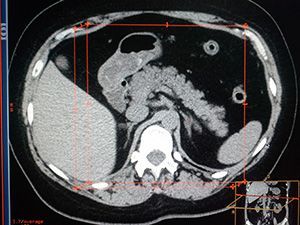

КТ или радионуклидное сканирование назначают для определения очагового стеатоза.

КТ органов брюшной полости

Стоимость: 9000 руб.

- органов брюшной полости.